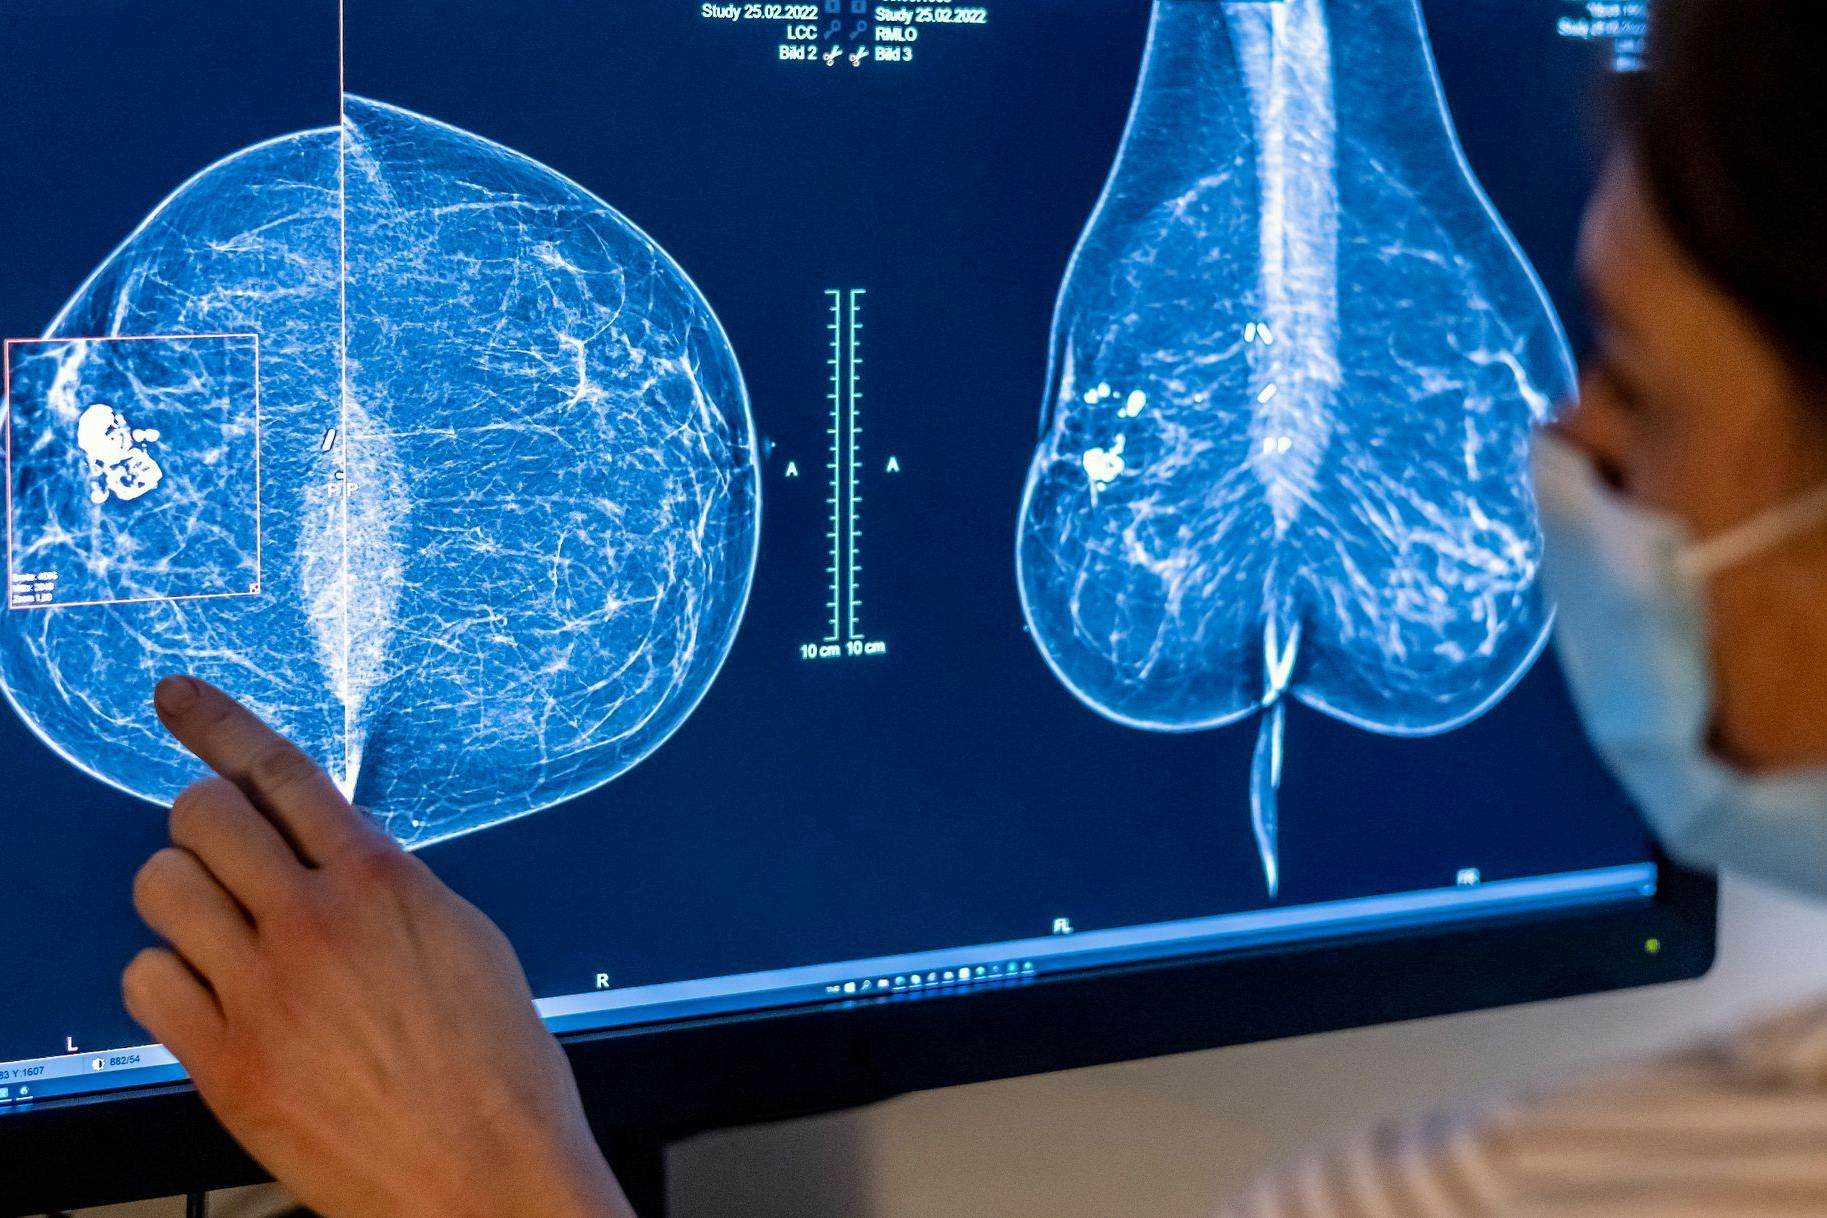

Die Landesgeschäftsführerin der Barmer Berlin/Brandenburg, Gabriela Leyh, warnte, Brustkrebs werde häufig zu spät erkannt, weil die Tumore zunächst keine Schmerzen verursachen. „Das Mammografie-Screening ermöglicht jedoch, dass Veränderungen an Brust und Brustwarze schon früh erkannt und medizinisch abgeklärt werden können“, sagte Leyh. Je früher Krebs erkannt werde, desto besser seien die Behandlungschancen. Bei der Mammografie erfolgt eine Röntgenaufnahme, mit der bereits kleinste, nicht tastbare Tumore in einem frühen Stadium entdeckt werden können.